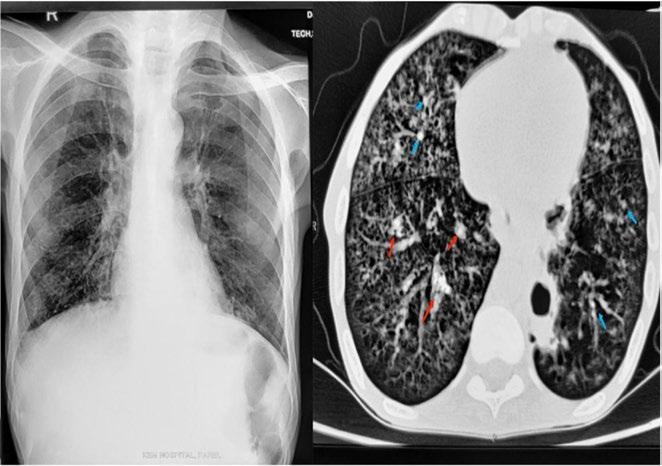

Lung cancer remains the leading cause of cancer-related death worldwide, largely due to late-stage diagnosis, explained Carlos F Muñoz-Núñez, La Fe University and Polytechnic Hospital, Valencia, Spain. He went on to say that approximately 75% of patients are diagnosed at Stage III and IV, and the global survival rate is less than 20% at 5 years.

Low-dose CT (LDCT) screening has been proven to reduce mortality in highrisk populations by enabling earlier detection. LDCT uses lower radiation doses than standard CT, making it suitable for repeated use, but it presents challenges such as image noise, false positives, and significant workload for radiologists.

AI offers promising solutions: improving risk-based population selection, enhancing image reconstruction with deep learning techniques, and supporting automated nodule detection and malignancy prediction. “Lung cancer based on risk models are tools designed to estimate an individual’s risk of developing lung cancer based on risk factors, and these models help guide screen decisions, early detection, and personalised prevention strategies,” he explained. AI can also help reduce overdiagnosis by integrating imaging with clinical, genomic, and biomarker data to identify indolent versus aggressive lesions.